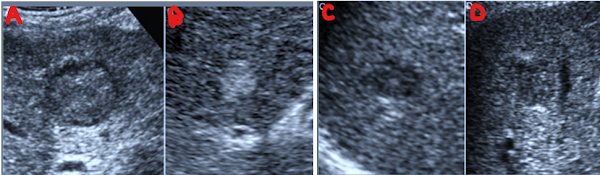

Larger HCCs often display the classic mosaic pattern—different internal densities, occasional halo, and possibly posterior acoustic enhancement

Large HCC generally appears as a solid, heterogeneous mass—often hypoechoic (darker) or mixed echogenic—and with ill-defined margins.

Massive HCC belongs to the “massive” growth type, typically >5 cm, often with necrotic areas and irregular borders.

Massive HCC typically arises in cirrhotic or chronically diseased livers and often presents late, sometimes with vascular invasion or satellite nodules.